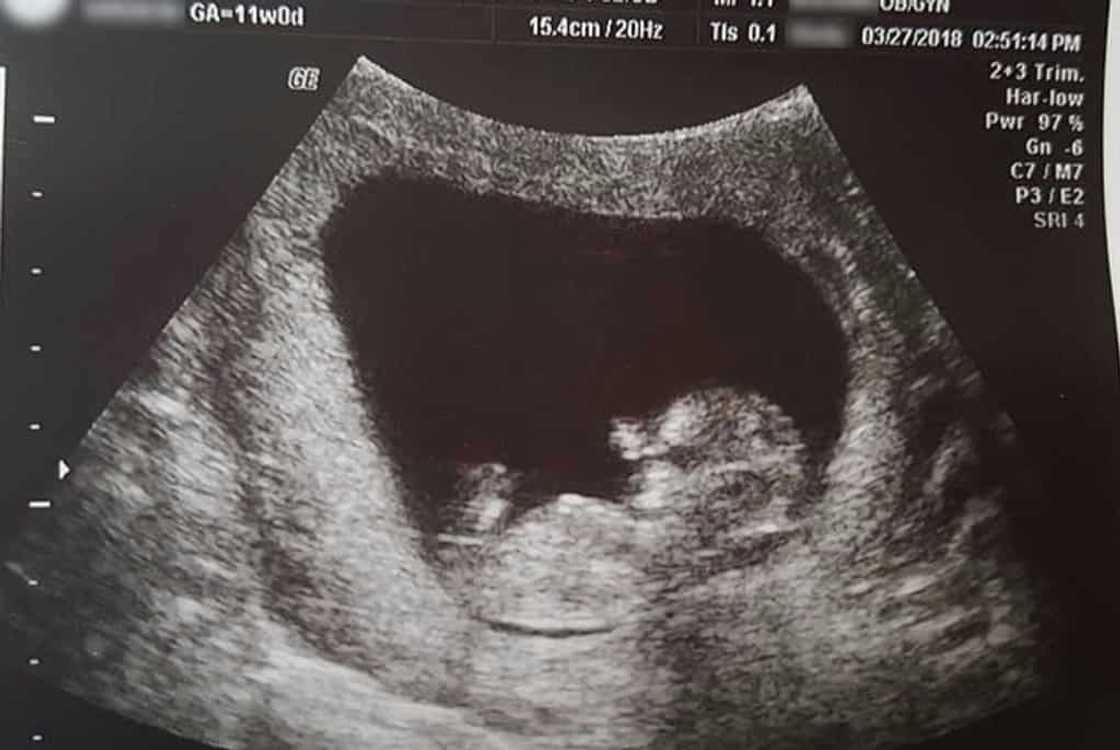

Kwento ni Felicia, sa ikatlong pagbubuntis, hindi nila inakalang mag-asawa na bibiyayaan sila ng kambal.

Ngunit nagkaroon siya ng mga problema sa pagbubuntis at pagkaraan ng anim na linggo, isa sa kambal ay namatay na sa kanya pa lang sinapupunan.

“We had not seen a doctor at that point yet; they don’t usually want to see you until you are eight or nine weeks. So I went into the hospital, bleeding, in fear of miscarriage.

They did an ultrasound and told us that we had lost one of two, but that the second baby looked healthy and strong. We had other scares when the bleeding started again and again but was told it was just due to the first loss and a hematoma beneath the placenta.

Japeth Peace Cash was born the morning of July 24th at 8:30, at home.” kwento nito kasama ang ilang mga larawan ng anak.

“Our beautiful Japeth Peace, miscarried July 24th at 14 weeks 6 days. He is perfectly and wonderfully formed, right down to his amazing tiny toes and fingers.

Even his fingernails are formed and visible. Tiny veins that carried his own blood to his precious body can be seen through his delicate skin, even his wonderfully formed muscles are visible. At less than half gestation he is very obviously human, not a cluster of cells, not a lump of tissue, not a blob of unformed flesh.

He is a beautiful child, formed by God, and now gone to be with Him. I am posting this in hopes of offering information to those who may not know how completely a child of only 14 weeks gestation is formed. And therefore not something to be taken lightly.” ani ng ginang sa isa pang FB post nito.